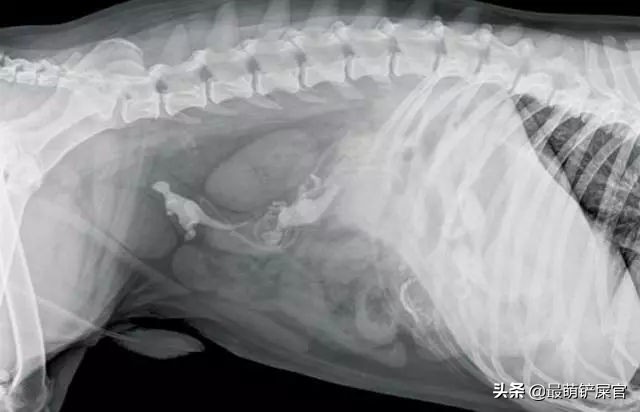

另外的一只狗狗说:吞针算什么?我可以把一个灯泡完好无损的吞下去!这可真是个技术活,也好在灯泡没有破裂,不然那些玻璃渣子划伤了食道和肠胃,那可不是在医院躺小半个月就能解决的了!